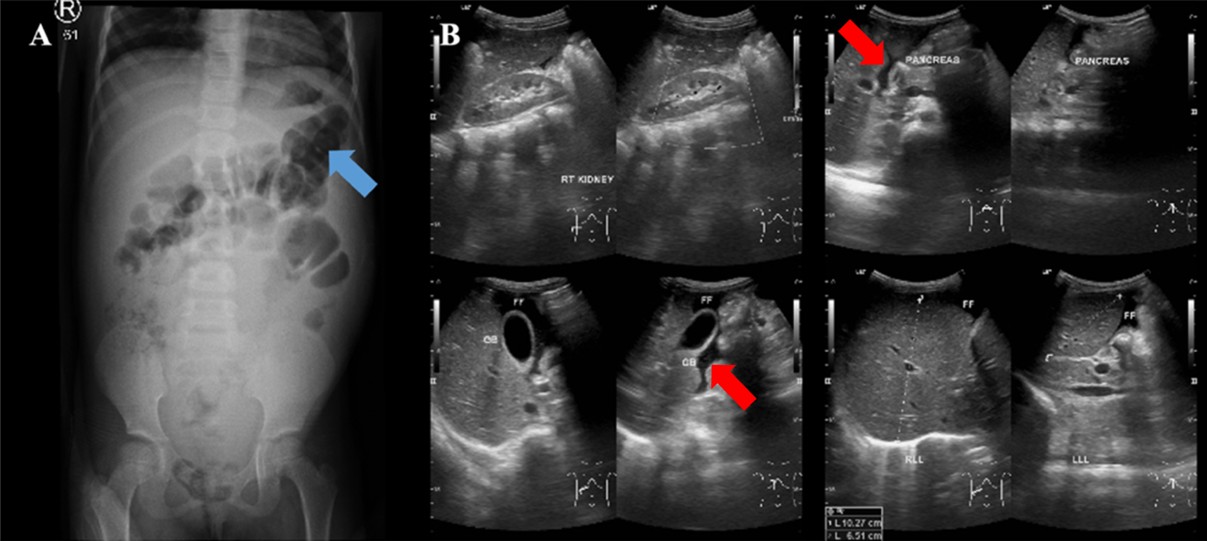

The abdominal X-ray showed distension and a sentinel loop in the left upper quadrant (Figure 1A), while the ultrasound revealed ascites (Figure 1B). The MTB/RIF Ultra (Cepheid, Sunnyvale, California, USA) test on sputum was negative, but a positive tuberculin test showed a 20 mm induration. A chest X-ray revealed hilar lymphadenopathy (Figure 2), giving a TB score of eight. Subsequently, to assess for extrapulmonary TB (EPTB), an ascitic fluid sample was obtained via laparoscopic examination. During the procedure, multiple whitish tubercles were observed (Figure 3A). Although the MTB/RIF Ultra test of the fluid was negative, the adenosine deaminase (ADA) level was elevated at 58 U/L, and histopathology confirmed abdominal TB with epithelioid granulomas and Langhans giant cells (Figure 3B). The HIV test was nonreactive.